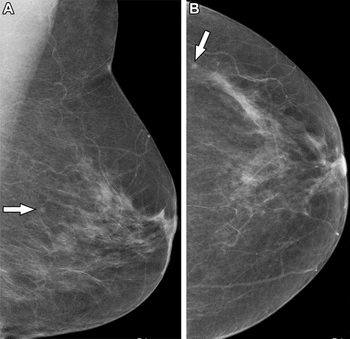

In separate test sets of Israeli women and United States women who had either ductal carcinoma in situ or invasive breast cancer, emerging artificial intelligence (AI) algorithms achieved an area under the curve (AOC) of 88 percent and 80 percent, respectively, for malignancy detection.